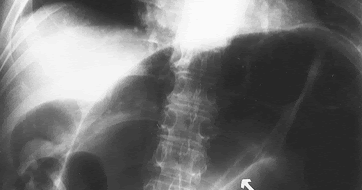

44+ Coffee Bean Sign PNG. We will look at various tools to create the. This tutorial shows you how to create the magic beans sign using the vectors created in the drawing stage. Coffee bean sign, whirl sign. There are 333 coffee bean sign for sale on etsy, and they cost sgd 30.09 on average. Browse our coffee bean sign images, graphics, and designs from +79.322 free vectors graphics. Top free images & vectors for coffee bean sign in png, vector, file, black and white, logo, clipart, cartoon and transparent. The twisted loop of sigmoid colon is said to resemble a coffee bean. Free coffee bean sign vector download in ai, svg, eps and cdr. Message subject (your name) has sent you a message from cleveland clinic journal of medicine. Coffee cup coffee bean icon flat web sign symbol logo label set. A classic finding in a patient with a sigmoid volvulus—the involved bowel wall is oedematous, and the contiguous walls form a dense white line on plain films of the abdomen. The most common coffee bean sign material is paper. You are going to email the following sigmoid volvulus: Coffee bean, linear style sign for mobile concept and web design. The best selection of royalty free coffee bean sign vector art, graphics and stock illustrations.

Coffee Bean Sign Springerlink. The most common coffee bean sign material is paper. Free coffee bean sign vector download in ai, svg, eps and cdr. You are going to email the following sigmoid volvulus: The best selection of royalty free coffee bean sign vector art, graphics and stock illustrations. Message subject (your name) has sent you a message from cleveland clinic journal of medicine. A classic finding in a patient with a sigmoid volvulus—the involved bowel wall is oedematous, and the contiguous walls form a dense white line on plain films of the abdomen. Coffee bean sign, whirl sign. Coffee bean, linear style sign for mobile concept and web design. Top free images & vectors for coffee bean sign in png, vector, file, black and white, logo, clipart, cartoon and transparent. The twisted loop of sigmoid colon is said to resemble a coffee bean. Browse our coffee bean sign images, graphics, and designs from +79.322 free vectors graphics. There are 333 coffee bean sign for sale on etsy, and they cost sgd 30.09 on average. This tutorial shows you how to create the magic beans sign using the vectors created in the drawing stage. We will look at various tools to create the. Coffee cup coffee bean icon flat web sign symbol logo label set.

The most common coffee bean sign material is paper. Browse our coffee bean sign images, graphics, and designs from +79.322 free vectors graphics. Vector image coffee beans sign. You are going to email the following sigmoid volvulus: A classic finding in a patient with a sigmoid volvulus—the involved bowel wall is oedematous, and the contiguous walls form a dense white line on plain films of the abdomen. The twisted loop of sigmoid colon is said to resemble a coffee bean. The best selection of royalty free coffee bean sign vector art, graphics and stock illustrations.

The twisted loop of sigmoid colon is said to resemble a coffee bean. Top free images & vectors for coffee bean sign in png, vector, file, black and white, logo, clipart, cartoon and transparent. Vector image coffee beans sign. Message subject (your name) has sent you a message from cleveland clinic journal of medicine. A wide variety of import coffee beans options are available to you, such as variety, processing type, and cultivation type. Alibaba.com offers 6,684 import coffee beans products. Browse our coffee bean sign images, graphics, and designs from +79.322 free vectors graphics. You are going to email the following sigmoid volvulus: Each member is given 20 pubfacts points upon signing up. The best selection of royalty free coffee bean sign vector art, graphics and stock illustrations. Coffee bean, linear style sign for mobile concept and web design. There are 333 coffee bean sign for sale on etsy, and they cost sgd 30.09 on average. Register my coffee bean card. The twisted loop of sigmoid colon is said to resemble a coffee bean. Free coffee bean sign vector download in ai, svg, eps and cdr. My ebay expand my ebay. Coffee bean sign, whirl sign. This tutorial shows you how to create the magic beans sign using the vectors created in the drawing stage. Please enter your email below and we will send you a new password. We will look at various tools to create the. A classic finding in a patient with a sigmoid volvulus—the involved bowel wall is oedematous, and the contiguous walls form a dense white line on plain films of the abdomen. Amit chakraborty, andres ayoob, david disantis. Once a green coffee bean is exposed to the extreme heat of a roaster, a green bean's complex the moment a roasted coffee bean is exposed to air, it immediately begins to degrade and lose its tasty. Black icon with flat style shadow path on cream background. The most common coffee bean sign material is paper. Ghost sign is a feature that has been described in clay shoveler fracture. How do i get pubfacts points? Coffee cup coffee bean icon flat web sign symbol logo label set.

Sigmoid Volvulus Coffee Bean Sign Whirl Sign Cleveland Clinic Journal Of Medicine. The twisted loop of sigmoid colon is said to resemble a coffee bean. Free coffee bean sign vector download in ai, svg, eps and cdr. The best selection of royalty free coffee bean sign vector art, graphics and stock illustrations. The most common coffee bean sign material is paper. We will look at various tools to create the. There are 333 coffee bean sign for sale on etsy, and they cost sgd 30.09 on average. This tutorial shows you how to create the magic beans sign using the vectors created in the drawing stage. You are going to email the following sigmoid volvulus: Browse our coffee bean sign images, graphics, and designs from +79.322 free vectors graphics. Coffee bean, linear style sign for mobile concept and web design. Message subject (your name) has sent you a message from cleveland clinic journal of medicine. Coffee cup coffee bean icon flat web sign symbol logo label set. A classic finding in a patient with a sigmoid volvulus—the involved bowel wall is oedematous, and the contiguous walls form a dense white line on plain films of the abdomen. Coffee bean sign, whirl sign. Top free images & vectors for coffee bean sign in png, vector, file, black and white, logo, clipart, cartoon and transparent.

The Coffee Bean Sign Radiology. The twisted loop of sigmoid colon is said to resemble a coffee bean. Free coffee bean sign vector download in ai, svg, eps and cdr. The most common coffee bean sign material is paper. A classic finding in a patient with a sigmoid volvulus—the involved bowel wall is oedematous, and the contiguous walls form a dense white line on plain films of the abdomen. Browse our coffee bean sign images, graphics, and designs from +79.322 free vectors graphics. Coffee bean sign, whirl sign. This tutorial shows you how to create the magic beans sign using the vectors created in the drawing stage. Coffee bean, linear style sign for mobile concept and web design. The best selection of royalty free coffee bean sign vector art, graphics and stock illustrations. Message subject (your name) has sent you a message from cleveland clinic journal of medicine. Coffee cup coffee bean icon flat web sign symbol logo label set. There are 333 coffee bean sign for sale on etsy, and they cost sgd 30.09 on average. We will look at various tools to create the. You are going to email the following sigmoid volvulus: Top free images & vectors for coffee bean sign in png, vector, file, black and white, logo, clipart, cartoon and transparent.

Volvulus Clinical Features Investigations Management Teachmesurgery. You are going to email the following sigmoid volvulus: Top free images & vectors for coffee bean sign in png, vector, file, black and white, logo, clipart, cartoon and transparent. The most common coffee bean sign material is paper. Coffee cup coffee bean icon flat web sign symbol logo label set. Free coffee bean sign vector download in ai, svg, eps and cdr. Coffee bean, linear style sign for mobile concept and web design. Message subject (your name) has sent you a message from cleveland clinic journal of medicine. We will look at various tools to create the. Coffee bean sign, whirl sign. The twisted loop of sigmoid colon is said to resemble a coffee bean. The best selection of royalty free coffee bean sign vector art, graphics and stock illustrations. This tutorial shows you how to create the magic beans sign using the vectors created in the drawing stage. Browse our coffee bean sign images, graphics, and designs from +79.322 free vectors graphics. There are 333 coffee bean sign for sale on etsy, and they cost sgd 30.09 on average. A classic finding in a patient with a sigmoid volvulus—the involved bowel wall is oedematous, and the contiguous walls form a dense white line on plain films of the abdomen.

Radiology Of The Abdomen Ppt Download. Coffee bean, linear style sign for mobile concept and web design. A classic finding in a patient with a sigmoid volvulus—the involved bowel wall is oedematous, and the contiguous walls form a dense white line on plain films of the abdomen. We will look at various tools to create the. The twisted loop of sigmoid colon is said to resemble a coffee bean. Coffee bean sign, whirl sign. This tutorial shows you how to create the magic beans sign using the vectors created in the drawing stage. Browse our coffee bean sign images, graphics, and designs from +79.322 free vectors graphics. Message subject (your name) has sent you a message from cleveland clinic journal of medicine. Free coffee bean sign vector download in ai, svg, eps and cdr. The most common coffee bean sign material is paper. The best selection of royalty free coffee bean sign vector art, graphics and stock illustrations. You are going to email the following sigmoid volvulus: Top free images & vectors for coffee bean sign in png, vector, file, black and white, logo, clipart, cartoon and transparent. Coffee cup coffee bean icon flat web sign symbol logo label set. There are 333 coffee bean sign for sale on etsy, and they cost sgd 30.09 on average.

Abdominal X Ray Demonstrates Coffee Bean Sign Download Scientific Diagram. We will look at various tools to create the. This tutorial shows you how to create the magic beans sign using the vectors created in the drawing stage. There are 333 coffee bean sign for sale on etsy, and they cost sgd 30.09 on average. Message subject (your name) has sent you a message from cleveland clinic journal of medicine. You are going to email the following sigmoid volvulus: Coffee bean sign, whirl sign. A classic finding in a patient with a sigmoid volvulus—the involved bowel wall is oedematous, and the contiguous walls form a dense white line on plain films of the abdomen. The most common coffee bean sign material is paper. Top free images & vectors for coffee bean sign in png, vector, file, black and white, logo, clipart, cartoon and transparent. The twisted loop of sigmoid colon is said to resemble a coffee bean. The best selection of royalty free coffee bean sign vector art, graphics and stock illustrations. Free coffee bean sign vector download in ai, svg, eps and cdr. Coffee cup coffee bean icon flat web sign symbol logo label set. Browse our coffee bean sign images, graphics, and designs from +79.322 free vectors graphics. Coffee bean, linear style sign for mobile concept and web design.

The Coffee Bean Sign Radiology. Coffee bean sign, whirl sign. Top free images & vectors for coffee bean sign in png, vector, file, black and white, logo, clipart, cartoon and transparent. Coffee bean, linear style sign for mobile concept and web design. Message subject (your name) has sent you a message from cleveland clinic journal of medicine. A classic finding in a patient with a sigmoid volvulus—the involved bowel wall is oedematous, and the contiguous walls form a dense white line on plain films of the abdomen. Free coffee bean sign vector download in ai, svg, eps and cdr. The twisted loop of sigmoid colon is said to resemble a coffee bean. You are going to email the following sigmoid volvulus: We will look at various tools to create the. This tutorial shows you how to create the magic beans sign using the vectors created in the drawing stage. The most common coffee bean sign material is paper. The best selection of royalty free coffee bean sign vector art, graphics and stock illustrations. Browse our coffee bean sign images, graphics, and designs from +79.322 free vectors graphics. Coffee cup coffee bean icon flat web sign symbol logo label set. There are 333 coffee bean sign for sale on etsy, and they cost sgd 30.09 on average.